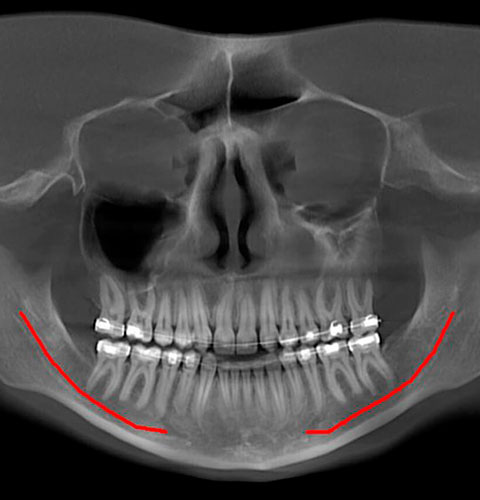

Veja exemplos de diagnósticos de imagem

- O gerador com ânodo giratório e ponto focal de 0,3 mm permite obter imagens de altíssima definição para ver detalhes e microestruturas que não podem ser investigados com dispositivos tecnológicos padrão;

- Algoritmos de reconstrução e processamento de imagem, resultado dos vinte anos de experiência da NewTom, permitem obter rapidamente imagens 2D e 3D excepcionais.

Com apenas algumas etapas simples, o NNT pode processar os dados adquiridos durante a varredura para criar uma vasta gama de imagens, que fornecem informações detalhadas sobre a anatomia do paciente. Posteriormente, eles podem ser salvos em um relatório ou distribuídos com a versão Viewer do software. O NNT também oferece diferentes modos de aplicação voltados especificamente para implantologia, endodontia, periodontia, cirurgia maxilofacial e radiologia.